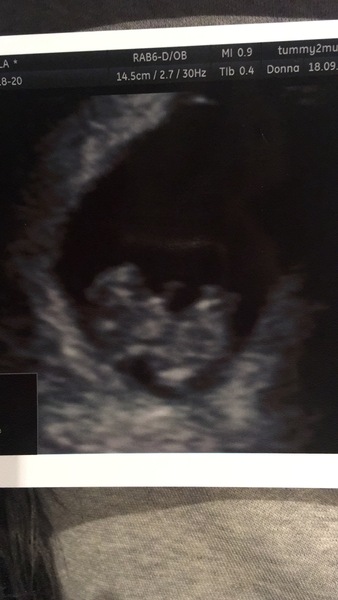

Hi ladies. Just thought I’d give you an update. Had a right scare on Friday. I started bleeding 😩 like red blood. Really panicked and got my Saturday morning scan brought forward to Friday night. Turns out baby was fine and it’s a hematoma which after googling looks to be a subchorionic bleed which I think I’ve read quite a lot on these forums. Mines only small at the moment (1cm) but still having brown which is never great to see. It was strange as it came out the blue and I had no pain but you still worry it’s a miscarriage starting. The sonographer/midwife was great though she searched and searched until she found it and she showed me my cervix is still closed. Just got to hope it stops now and sorts itself out, apparently they usually reabsorb as they are like a bruise on the outside of the uterus. I think the fact I’m still having brown now might mean it’s still bleeding just slowly at the moment. Il attach a scan picture, the baby gave us a wave as it’s hit arms and legs etc and wriggling about ❤️ Measuring 9+1 on Friday and I’m 9+4 today. One day at a time...

Hi all, I hope everyone is getting on okay. I've been quietly reading along whilst taking a step back a bit this month from all things ttc but just wanted to say @Pugprincess what's a gorgeous scan pic!! So pleased for you 💕 I bet you were terrified but I'm really glad you know the cause of the bleed.